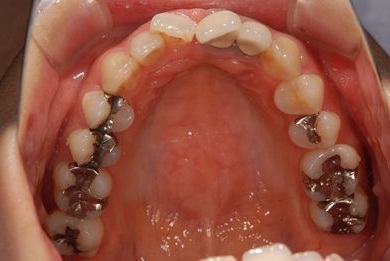

| 性別/年齢 | 女性 / 31歳 | ||||||||||||||||||||||||||||||||

| 主訴 | 前歯の歯茎が黒ずんでいるので、改善したい。 | ||||||||||||||||||||||||||||||||

| 治療方針 | 上顎前歯、メタルボンドセラミッククラウンからオールセラミッククラウンにする事で、審美的回復を行う。 | ||||||||||||||||||||||||||||||||

| 治療内容 | CAD/CAMオールセラミッククラウン2本(セラミック用土台2本) | ||||||||||||||||||||||||||||||||

| 総治療費 | 142,800円 | ||||||||||||||||||||||||||||||||

| 治療期間 | 2ヶ月 |